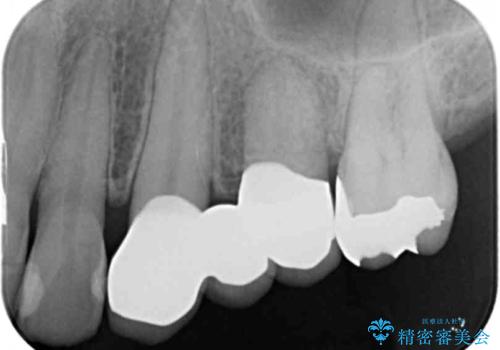

ブリッジの長期的な予後のためには支台となる歯の位置・清掃性が重要となりますが、今回ブリッジを製作するにあたり位置の悪い左上小臼歯を補綴前小矯正を行い位置を改善します。

- 47.3万円(仮歯・ジルコニアクラウン×3 ・ 小矯正)費用は治療当時の料金となります

補綴前小矯正について

矯正を行うことで歯を適切な位置に動かすことでより、清掃性に優れ長期的な予後を見込むことのできるブリッジを製作することができました。